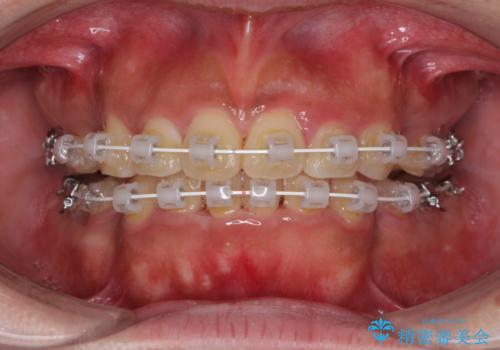

- 審美装置

- 口元の突出感と上下前歯のでこぼこを気にして来院された患者様です。

上下前歯部叢生のスペース獲得のため、上下顎左右小臼歯各1歯(計4本)を抜歯して、矯正治療を行うこととしました。

口腔内の清掃性に問題があり、虫歯のリスクが極めて高かったため、短期で治療を終えることを最優先に治療を進めました。